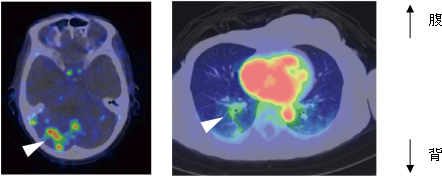

臨床試験では、既にHER2陽性であることが確認され、トラスツズマブで治療中の乳がん患者の協力を得ました。文書による臨床試験への参加同意が得られた患者14症例に対して、通常治療用量の100分の1以下※9に相当する64Cu-DOTA-Trastuzumabを静脈注射し、6、24、48時間後にPET検査を行いました。その結果、最小直径2.0cmまでの腫瘍を描出できることが分かり、ほとんどの症例でHER2陽性乳がんの原発巣に一致したシグナルを観察しました(図2)。転移巣の診断では、特に脳転移の描出に優れることが分かりました(図3左)。針生検でHER2陽性乳がんの肺転移が確定した症例では、転移巣の位置にシグナルを認め、針生検と画像診断の結果が一致することを確認しました(図3右)。また胸骨/縦隔リンパ節転移症例では、治療に伴いがん組織が縮小する様子を追跡できました(図4)。さらに、腎細胞がんとHER2陽性乳がんの両方のがんを有する症例(重複がん)では、HER2陽性脳転移巣が描出される一方、腎細胞がんではシグナルを認めず、今回のPET検査がHER2陽性腫瘍を特異的に検出することが分かりました。

図3 HER2陽性乳がん転移巣でのトラスツズマブPETプローブの集積

64Cu-DOTA-Trastuzumabの体内動態を全身にわたって追跡したところ、3症例で脳転移が疑われるシグナルを観察した(写真左、矢頭)。また、針生検で肺転移が確定した患者では、肺転移巣に一致したシグナルを観察した(写真右、矢頭)。写真右の中央部の赤い部分は血中のシグナル(心臓内腔)を示す。